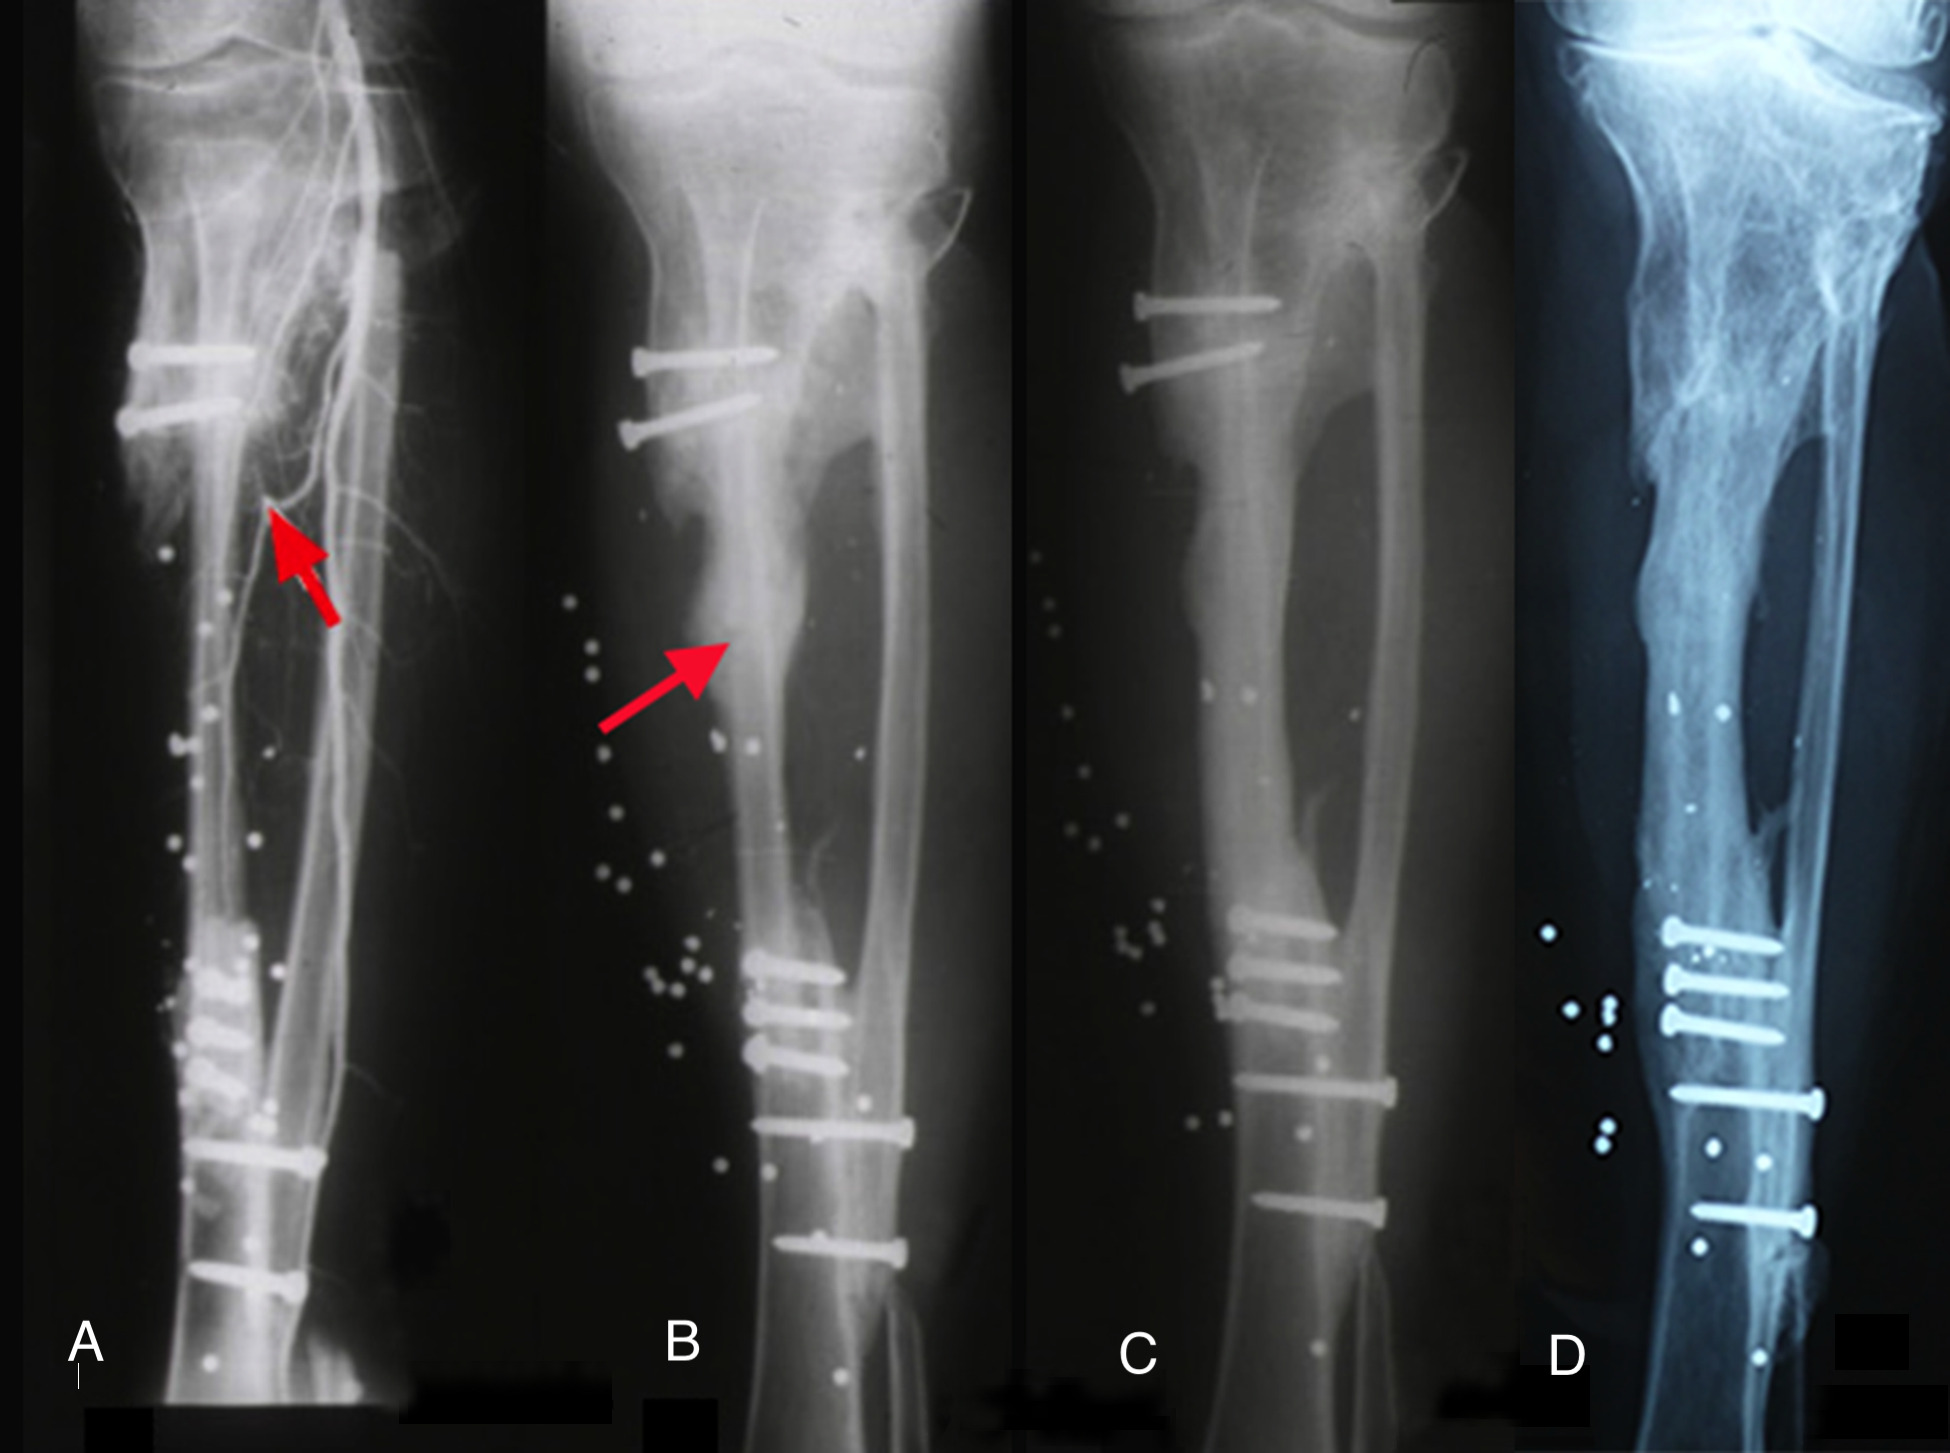

On 20 January 1973 the free groin flap was transferred successfully at PANCH for the first time.2,3 One week later, a 19-year-old young man was admitted to the same hospital with a shotgun injury to his left leg (Figure 1A). The wound included skin, most of the anterior muscle compartment and a 12.5 cm defect of the tibia (Figure 1C).

The foot was sensate and the fibula was intact. So we set about reconstruction. The defect was debrided, healed initially with a split skin graft and then a free groin flap was attempted but abandoned because the groin vessels were very small and the recipient anterior tibial vessels badly damaged. However, because we had performed a lateral to medial dissection of what was now an expanded iliofemoral flap,2 that included the superficial inferior epigastric as well as the superficial circumflex iliac vessels, we were able to tube the flap and transfer it in stages to the leg (Figure 1B).

A two-stage transfer of the ipsilateral fibula was then attempted by our orthopaedic team, based on a muscle pedicle and fixed to the tibia with screws. Unfortunately, the bone failed to knit at the upper end. It developed a pseudarthrosis and the patient was left with a flail leg (Figure 2). Amputation was recommended but ‘if a skin flap can be transferred successfully with microsurgery why not bone, and which one?’

Both legs were placed in above-knee casts and the postoperative course was uncomplicated. The cast was removed from the donor right leg at three weeks and left on the other for six months. At five weeks an angiogram revealed a patent anastomosis (Figure 4A) and a bone biopsy revealed living osteocytes. At nine months the patient received an injury to his transplant when a door of a vehicle was slammed on his leg. The leg was a bit sore but he was able to walk with some discomfort. He presented a month later when an X-ray revealed not only a stress fracture, but showed callus and bony union in this transplanted fibula (Figure 4B)! Thereafter, remarkably in just two months, the fibula doubled its diameter! Subperiosteal thickening had occurred along its entire length, like wax dripping down a candle (Figure 4C). Notably, when reviewed 40 years later the original medullary cavity of the transplanted fibula was still visible (Figure 4D), with normal activity in both legs (Figure 5).6